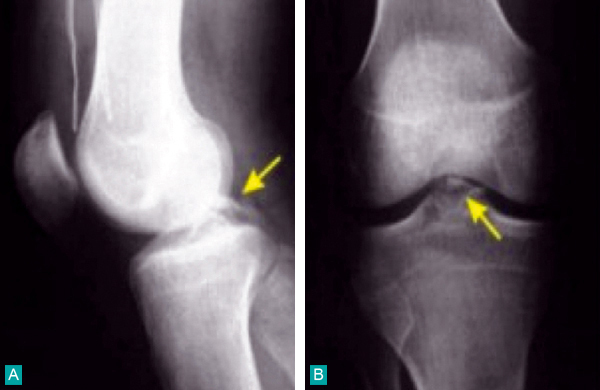

Lésions osseuses radiologiques d'une rupture du ligament croisé antérieur

A. Profil : avulsion du massif des épines tibiales.B. Face : fracture de Segond.